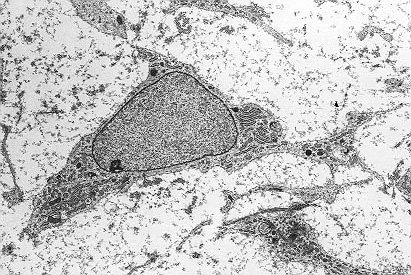

Células madre mesenquimales. (Foto: Robert M. Hunt)

Estudios previos en animales y humanos habían sugerido el potencial de las células madre mesenquimales de la médula ósea, también conocidas como células estromales o MSC –por sus siglas en inglés- en el tratamiento del lupus, ya que se considera que la enfermedad puede ser producto de una alteración en el tejido mesenquimal, aquel que da lugar, por ejemplo, a huesos, músculos o cartílagos.